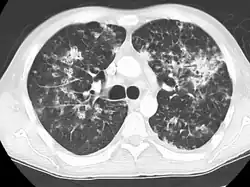

CT, showing extensive pulmonary parenchymal involvement consisting of irregular septal thickenings with ground-glass areas and centrilobular nodules with a peri-lymphatic distribution -

Miliary tuberculosis is a form of tuberculosis that is characterized by a wide dissemination into the human body and by the tiny size of the lesions (1–5 mm). Its name comes from a distinctive pattern seen on a chest radiograph of many tiny spots distributed throughout the lung fields with the appearance similar to millet seeds—thus the term "miliary" tuberculosis. Miliary TB may infect any number of organs, including the lungs, liver, and spleen.[5] Miliary tuberculosis is present in about 2 percent of all reported cases of tuberculosis and accounts for up to 20 percent of all extra-pulmonary tuberculosis cases.[6]

Testing for miliary tuberculosis is conducted in a similar manner as for other forms of tuberculosis, although a number of tests must be conducted on a patient to confirm diagnosis.[7] Tests include chest x-ray, sputum culture, bronchoscopy, biopsy, CT/MRI, blood cultures, fundoscopy, and electrocardiography.[1] The tuberculosis (TB) blood test, also called an Interferon Gamma Release Assay or IGRA, is a way to diagnose latent TB.A variety of neurological complications have been noted in miliary tuberculosis patients—tuberculous meningitis and cerebral tuberculomas being the most frequent. However, a majority of patients improve following antituberculous treatment. Rarely lymphangitic spread of lung cancer could mimic miliary pattern of tuberculosis on regular chest X-ray. [14][4]